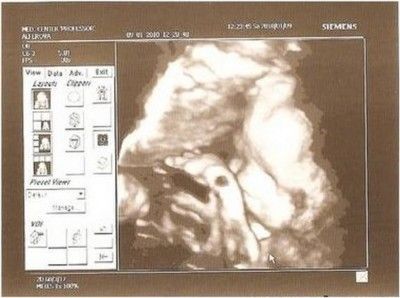

На 12 тижні помітних відмінностей між статевими органами хлопчика і дівчинки немає. Статевий горбок і статеві складки оточені зовні губно-мошоночних горбками.

Хлопчик зліва і дівчинка справа. Погодьтеся, картинки не сильно відрізняються?

Правильна візуалізація будь-якій частині плода залежить від багатьох факторів, таких як стан плода, кількість амніотичної рідини і товщина черевної стінки. Такі вдалі картинки як на фото зліва виходять украй рідко. У кого більше?

На УЗД, якщо дитина добре повернувся, підлога може бути визначений на терміні 12 тижнів після зачаття (14 акушерських).

Визначення відбувається за рахунок аналізу кута між статевим горбком і спинкою малюка.

12-тижневий ембріон - (розмір ембріона 75 мм) - 14 акушерських тижнів вагітності

хлопчик

Досвідчені УЗД фахівці можуть визначити стать, вимірявши кут статевого горбка.